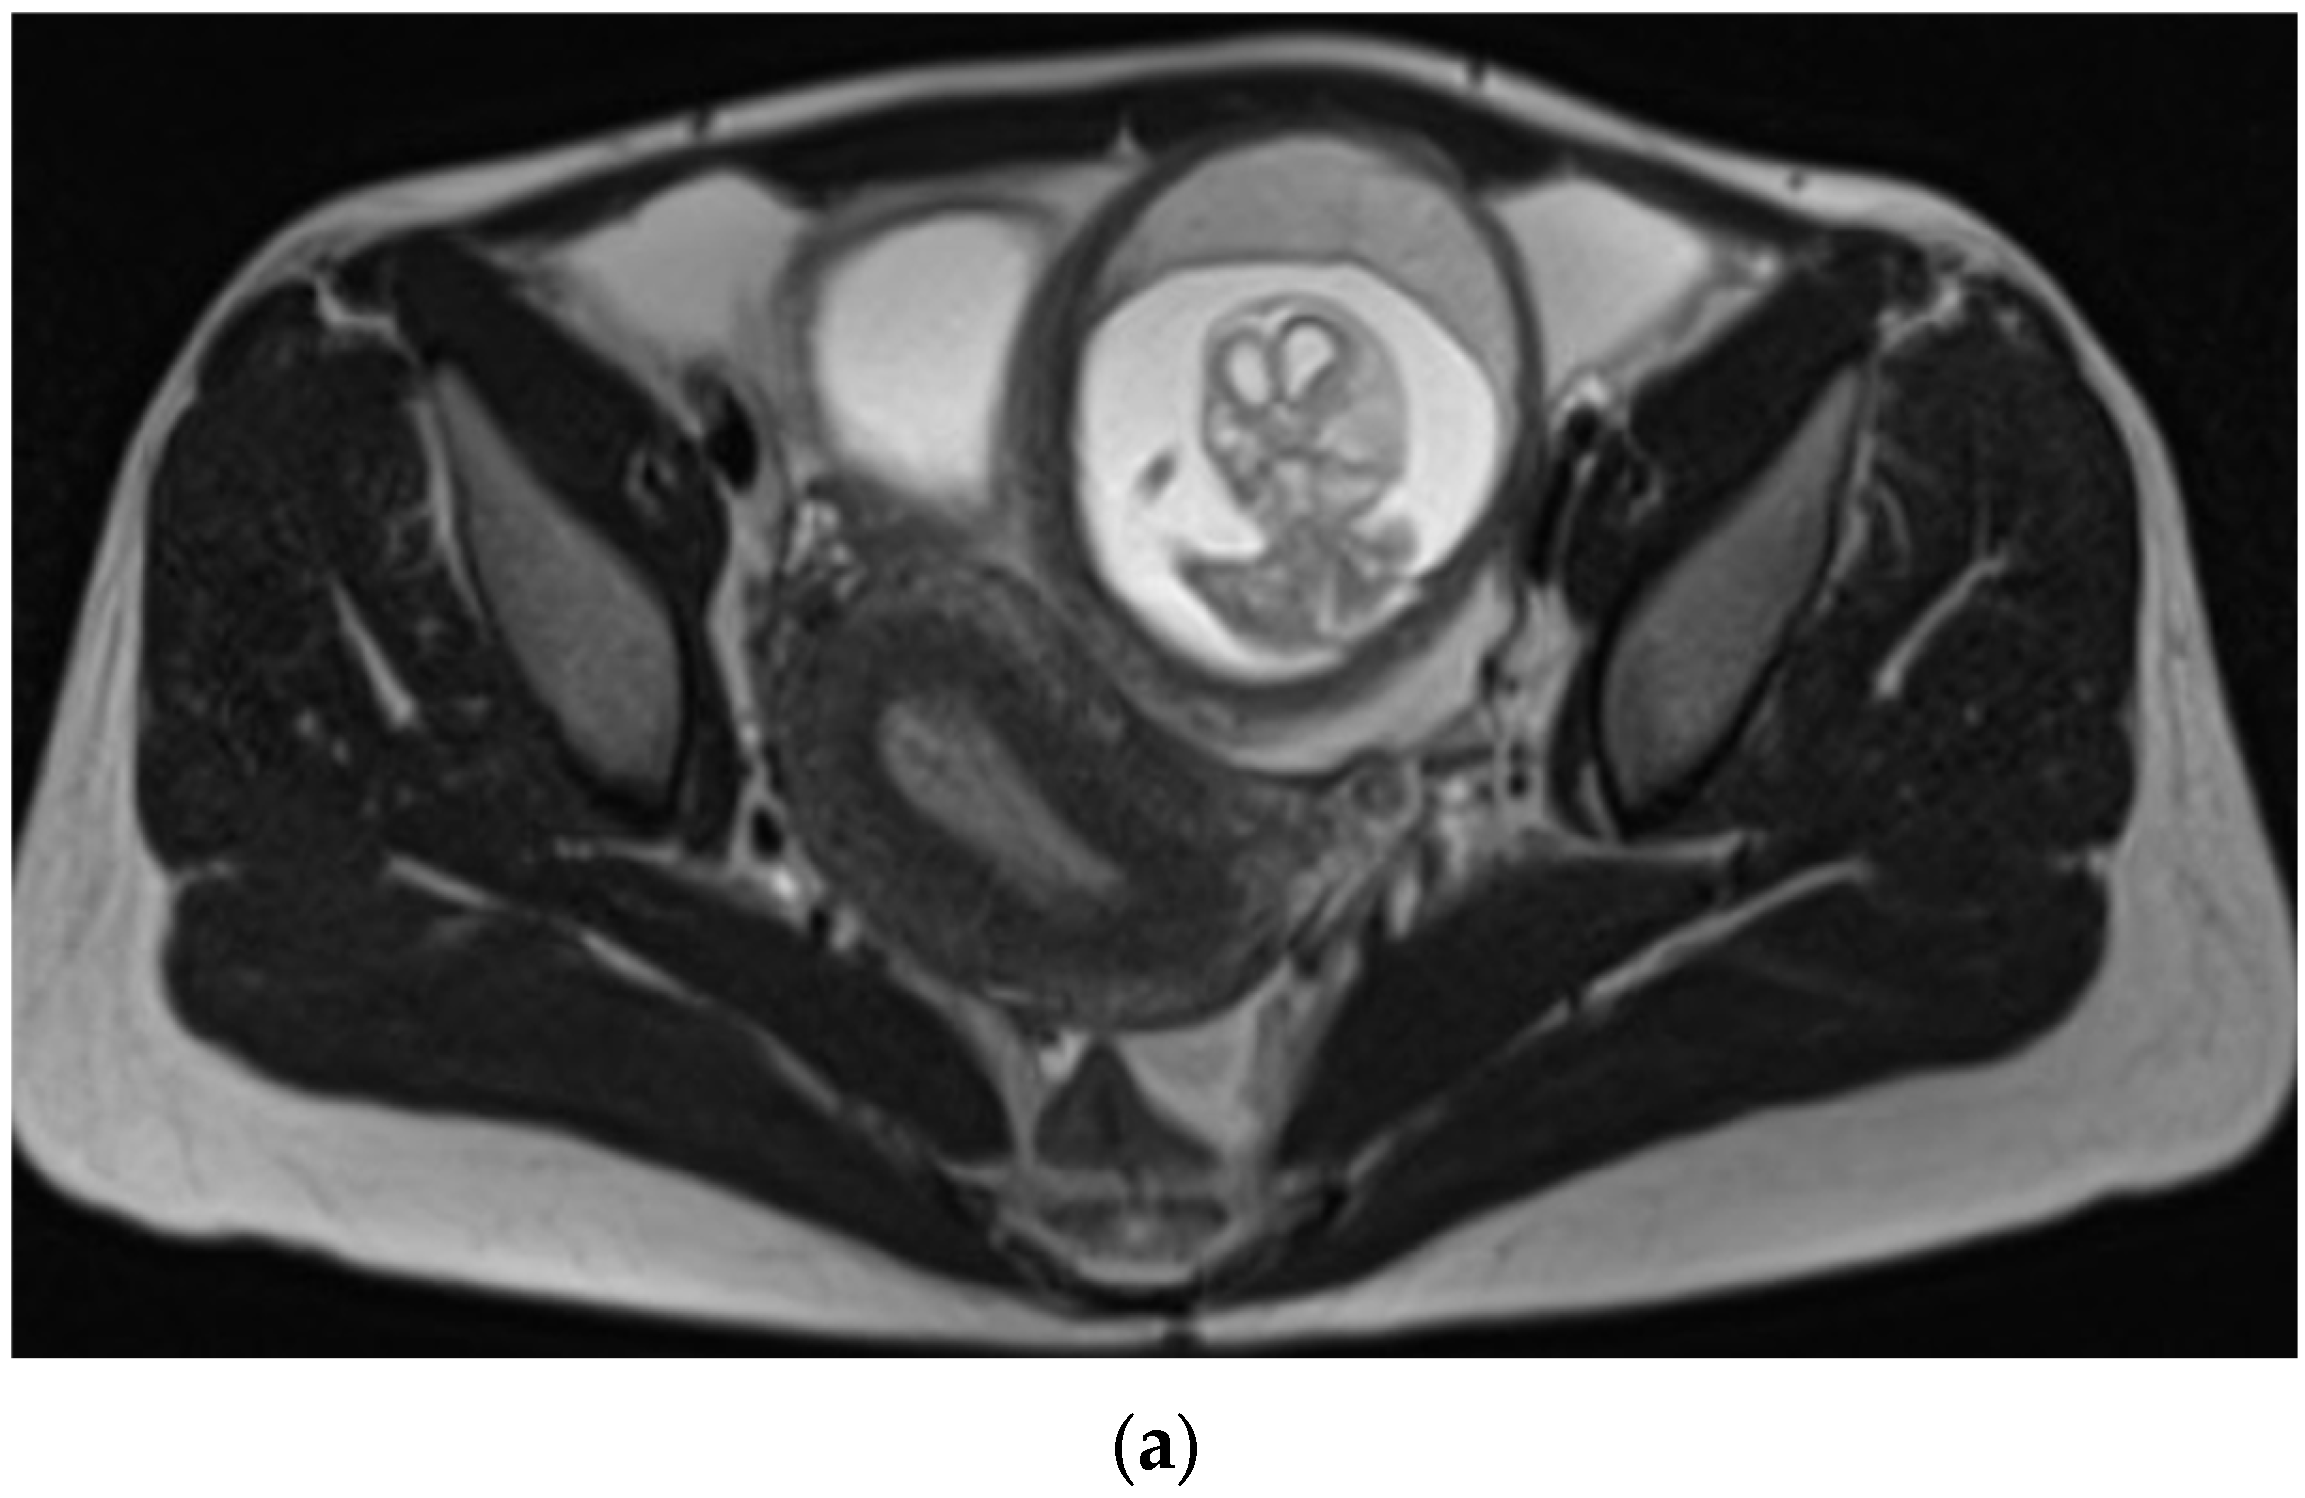

Figure 2.

MRI without contrast showed that the ectopic gestational sac exerted mass effect upon the uterus and bladder, and was associated with a moderate amount of pelvic fluid. (a) Axial T2 HASTE demonstrating ectopic pregnancy in the left adnexa with associated mass effect on the bladder and uterus which deviate to the right. The placenta is located anteriorly within the gestational sac. (b) Sagittal T2 HASTE demonstrating ectopic pregnancy located anterior to uterine fundus and superior to bladder. The anterior wall of the gestational sac is located approximately 1.3 cm deep to the overlying skin surface. There is a moderate amount of complex free pelvic fluid. (c) Coronal T2 HASTE demonstrating intact gestational sac superior to the bladder in the left adnexa. The left ovary is partially visualized superior to the gestational sac and contains an incidental 2.0 cm follicle.